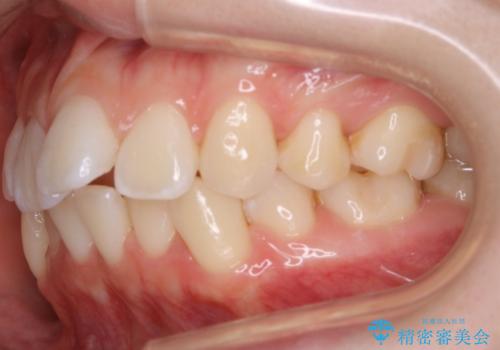

- 以前、中学生から高校生にかけてワイヤー装置による抜歯矯正を経験されている患者さんで、大人になってからのライフスタイルの変化でリテーナーを継続使用することができず、ガタつきが目立つようになってきてしまったのでもう一度矯正治療がしたいという主訴でご来院されました。

既に上下左右の4番目の歯が抜歯されているため、今回の治療では抜歯をせず歯の移動だけでガタつきを治す必要があり難易度が高くなっていました。